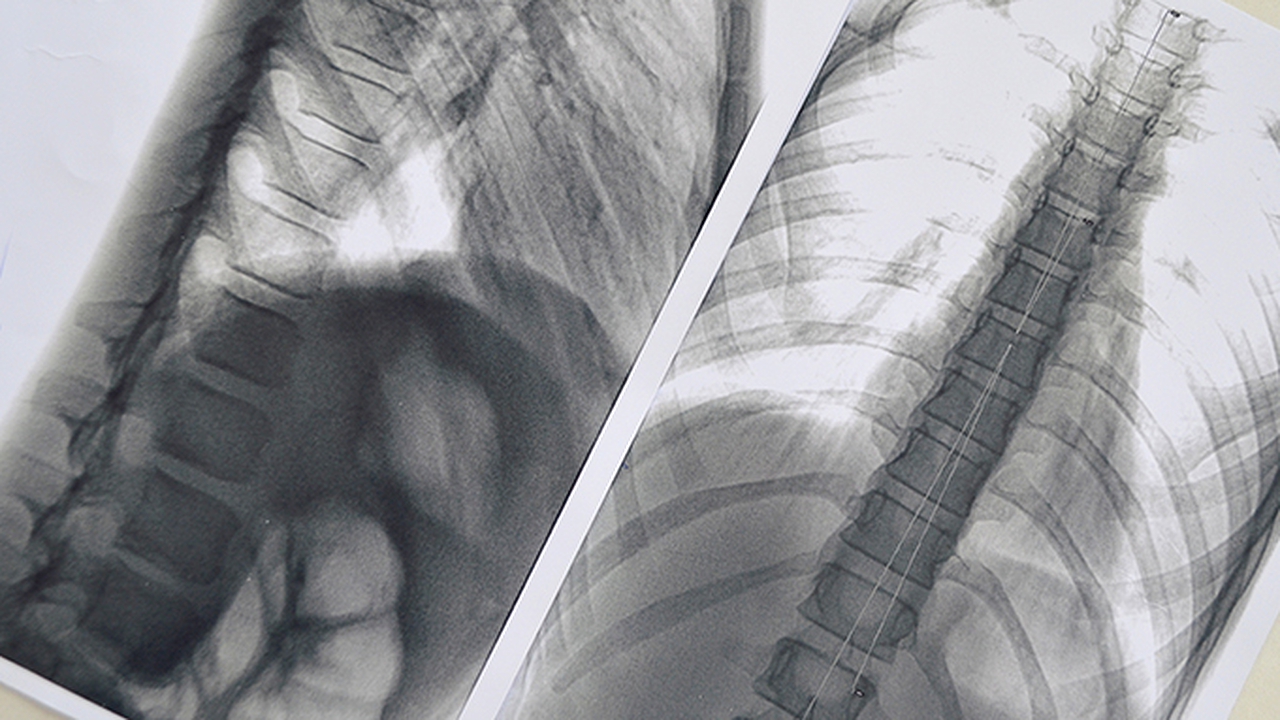

少数情况下,肺炎支原体感染可能引发严重并发症。患者可能出现大叶性肺炎,表现为高热、剧烈咳嗽、胸痛等症状。个别患者可能发生胸腔积液,导致呼吸困难加重。免疫功能低下者可能出现重症肺炎,甚至需要住院治疗。儿童患者可能出现喘息、气促等表现,严重时可能影响正常活动。